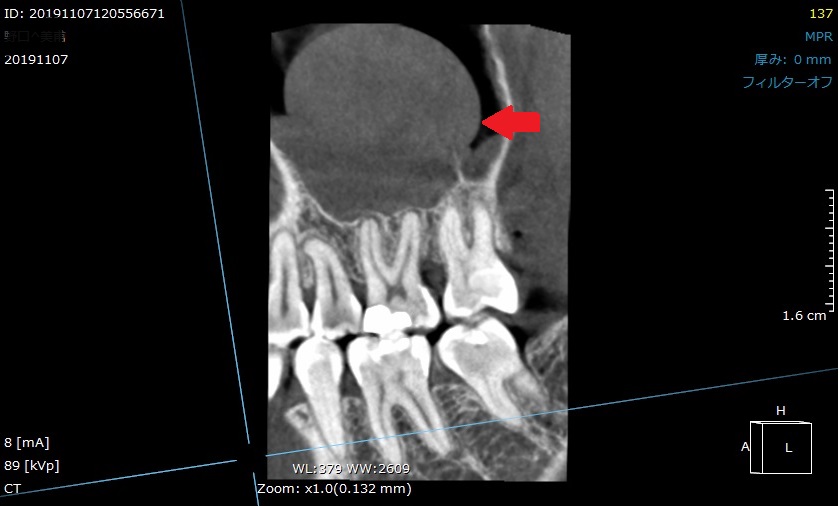

正面からの画像です。CT撮影は様々な方向から確認できます。

矢印の所にドーム状のふくらみが認められます。

原因は、虫歯の細菌が神経内部に感染し、

根の先まで侵入し、炎症を起こしている状態です。

「歯性上顎洞炎」と診断名が付きます。

歯の神経の感染が原因なので、

根管治療により、細菌の除去、感染している神経を取り除きます。